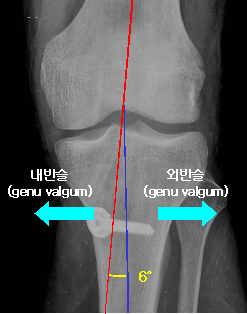

1) 하지의 정열

• 내반슬(genu varus) : O자 다리 - 양 발목 사이가 9-10cm 이상

• 외반슬(genu valgum) : X자 다리 - 양 슬관절 사이가 4cm 이상

• 경대퇴골간 각(tibiofemoral shaft angle) : 6도